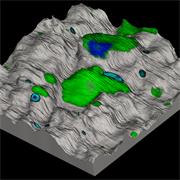

- Generate images of the formulations used in tablets, inhalers and nasal sprays at sub-micrometre spatial resolution

Generate images of formulations

Ensure your chemical images are representative; use Renishaw's StreamLine. You can change resolution to suit your domain size and, because Renishaw's WiRE software can cope with massive data files, you can analyse over the entire sample surface. Powerful Renishaw features, such as Slalom (to ensure the whole surface is sampled) and HD imaging (to get crisp clear images), provide all the options you need, whatever your formulation.